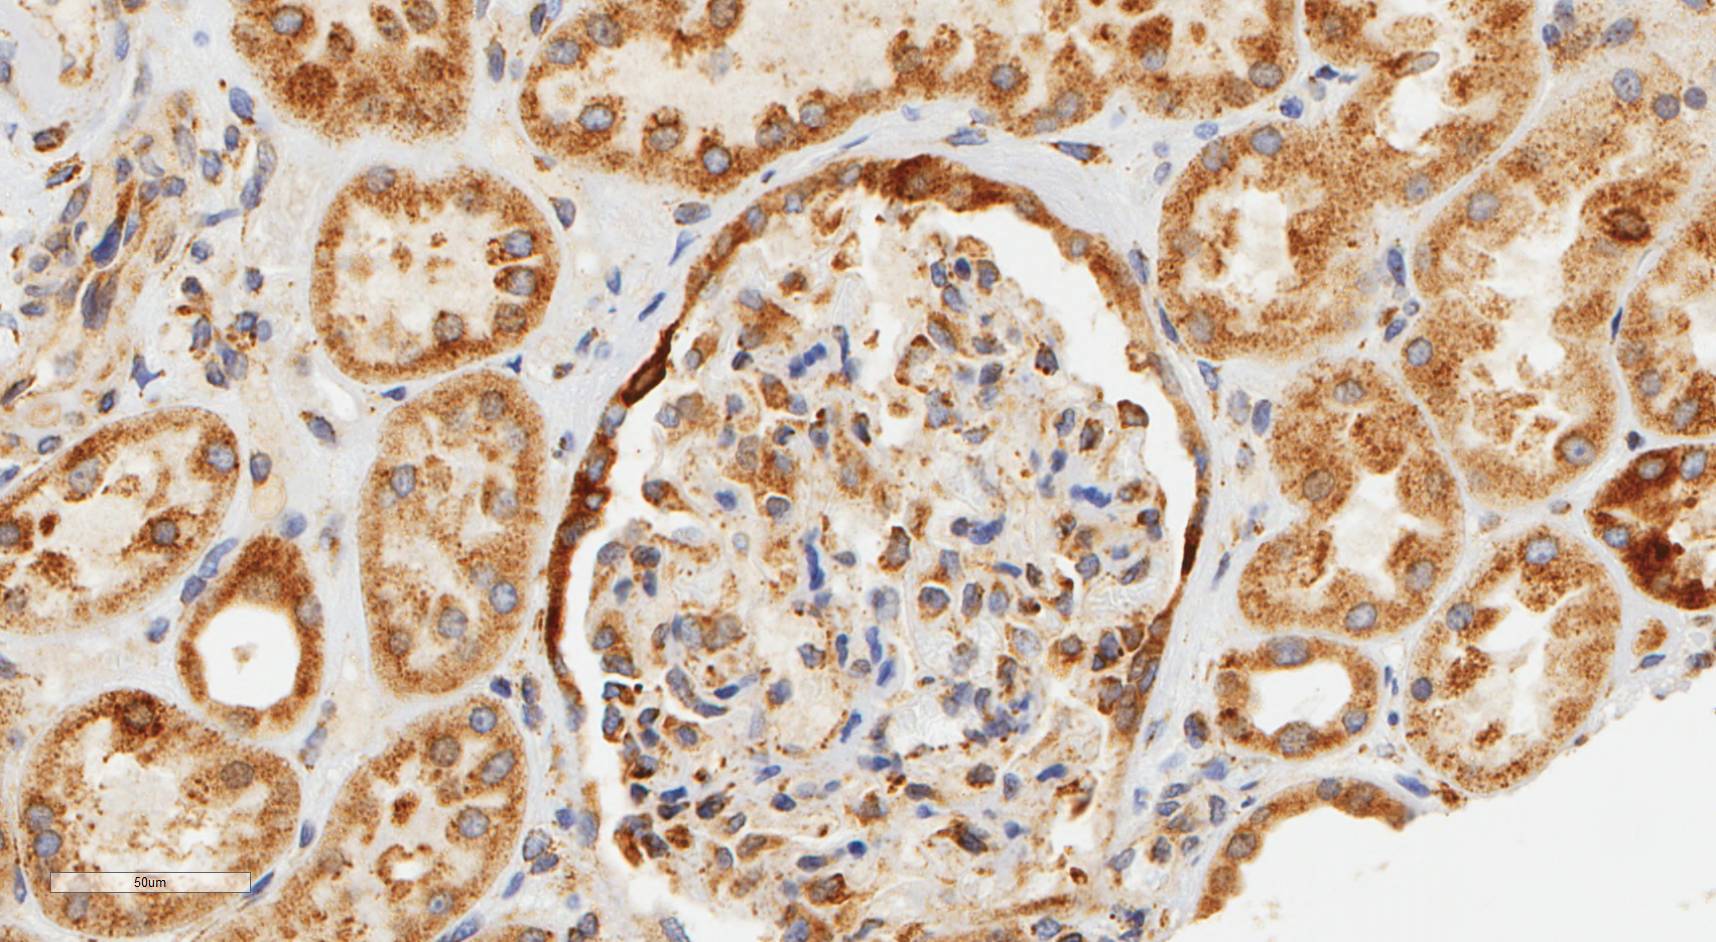

Laminin N terminus alpha31 (LaNt a31) is a really interesting laminin-related protein that the Hamill lab has been investigating for a while. Until recently, our studies focused entirely on the epithelial tissues of the skin, the surface of the eye and oral squamous cell carcinoma. However, we’ve always known that this relatively unstudied protein is also expressed by other tissues. As a first (and really important) step to understanding what this protein’s role is in tissue function, we used our new mouse monoclonal antibodies against the human form of LaNt a31 to screen a wide-range of human tissues.

Below you can see some of our favourite images from the selection. Click on an image to view as a slideshow.

You can see the whole story in the paper by Lee Troughton et al., available here.